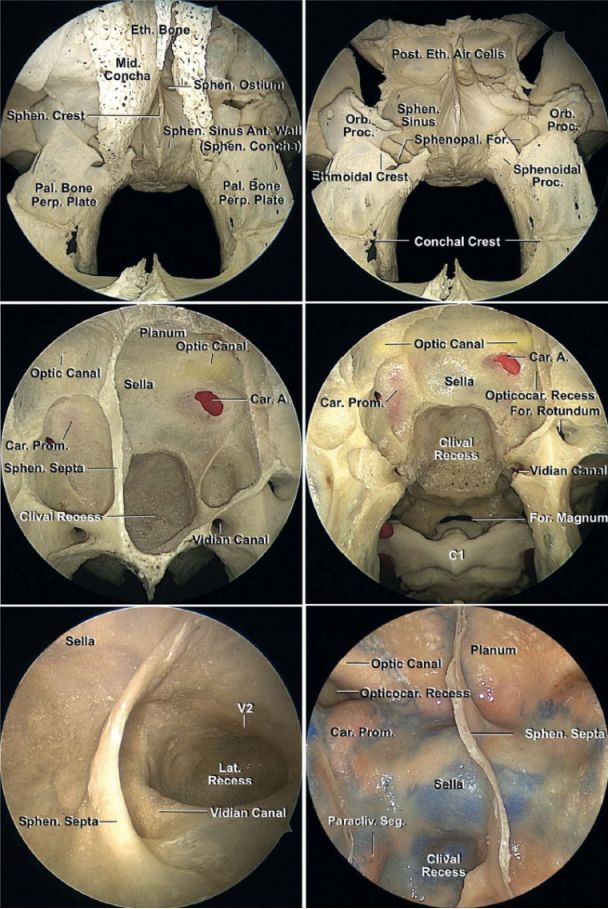

图4:内镜下经鼻入路的中线骨性解剖。筛骨垂直板、犁骨和蝶骨嵴构成鼻中隔骨性部分。蝶腭孔位于鼻腔外侧壁筛骨嵴的上方,颚骨蝶突和眶突之间(右上图)。蝶窦后壁的解剖结构:翼管在蝶窦的下外侧角(左中图)。45°内镜下的蝶窦右侧壁(左下图)。另一标本上蝶窦后壁解剖结构(右下图)。(图片由AL Rhoton, Jr提供)。

图5:暴露右侧斜坡下段(上排图)。颈内动脉垂直段沿着蝶窦后壁的外侧缘,称为斜坡旁段,岩部颈内动脉破裂孔段位于颈内动脉前膝以远。斜坡中下段后部保留有薄层硬膜桥作为分界(下排图)。(图片由AL Rhoton, Jr提供)。

图6:逐层显露斜坡上段解剖结构。海绵窦内侧壁已切除。注意经斜坡入路所显露的相关神经血管结构。许多软骨肉瘤包饶斜坡旁段和岩骨段颈内动脉并侵入海绵窦。(图片由AL Rhoton, Jr提供)。

图7:内镜下斜坡中段的解剖结构。45°内镜下观察破裂孔区,切开翼管(上排图)。斜坡右侧部骨质被磨除,去除硬膜,可以看见斜坡上中段的硬膜桥分界线和斜坡中下段的薄层骨桥分界线(中排图)。45°内镜近距离观察斜坡的一侧(左下图),磨除岩尖和颈动脉管远端下面的骨质后暴露第Ⅶ/Ⅷ颅神经复合体脑池段(右下图)。(图片由AL Rhoton, Jr提供)。

图8:右侧斜坡下部解剖结构(左上图)。注意后组颅神经的相关解剖。双侧斜坡下部切除后解剖结构(右上图)。可见延髓前表面、椎动脉、小脑后下动脉、脊髓前动脉(上排图)。其他中线矢状位标本,显露了鼻咽后部及其相关肌肉和斜坡下段(下排图)。(图片由AL Rhoton, Jr提供)。